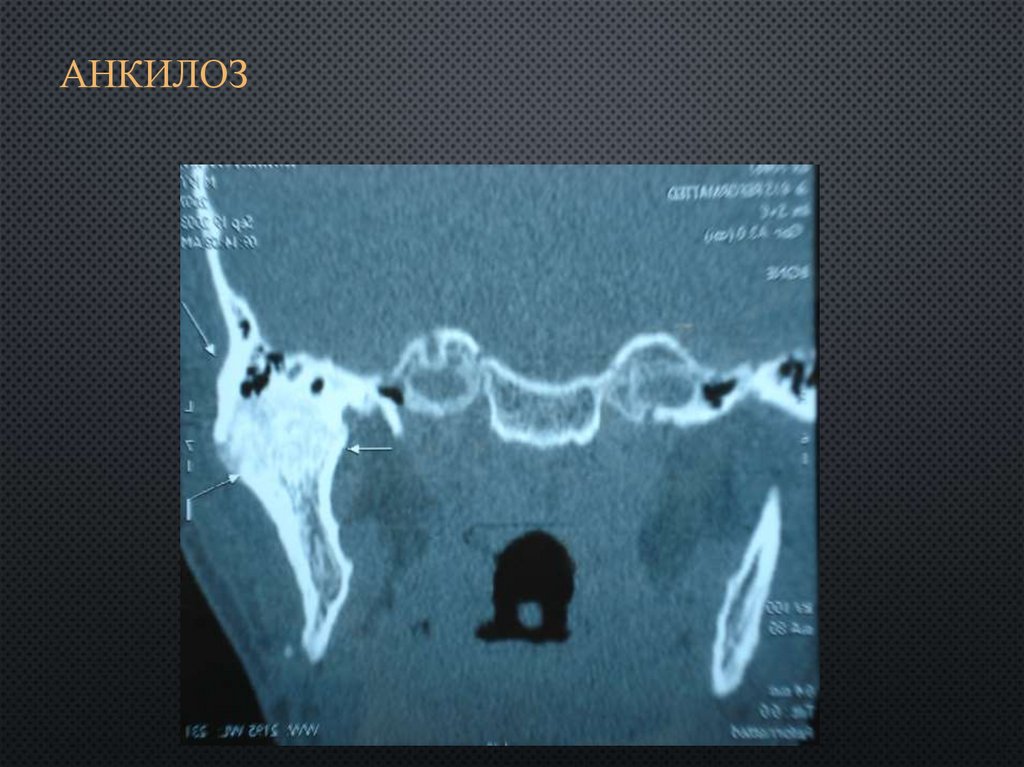

Рентгеновские снимки анкилоза суставов: Как это выглядит